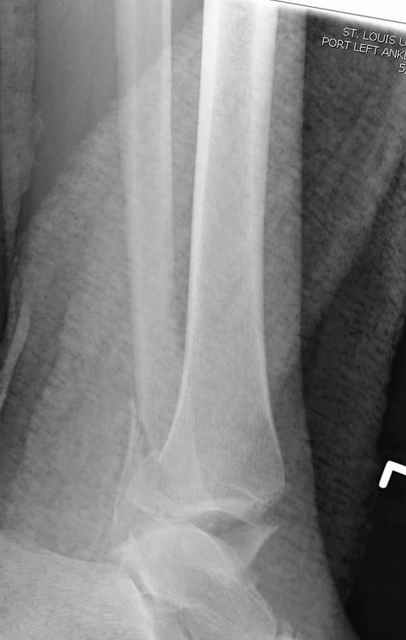

Pilon fracture:

Дистракция в аппарате или на вытяжение результат - лигаментотаксис, посмотреть бы, как сегодня расположены отломки.